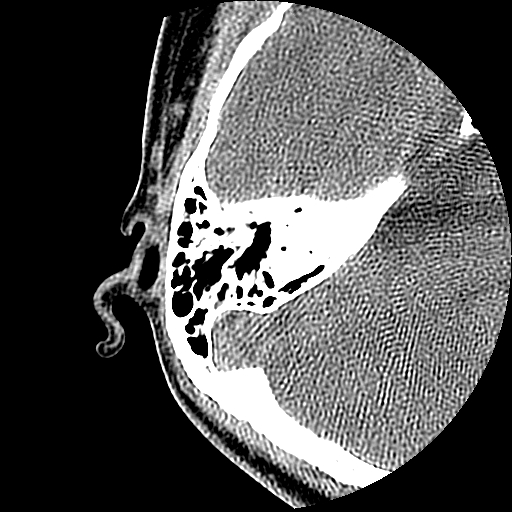

以下是引用随光逐影在2009-8-19 7:25:00的发言:[br]右侧慢性中耳乳突炎,右侧中耳腔及外耳道肉芽肿或胆脂瘤形成。